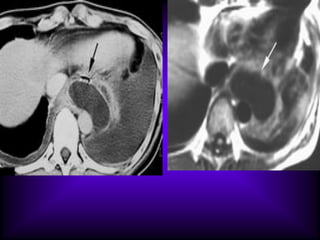

The CT features of benign

mediastinal cyst are

(a) a smooth, oval or tubular mass with a well-

defined thin wall that usually enhances after

intravascular administration of contrast

material,

(b) homogeneous attenuation, usually in the

range of water attenuation (0–20 HU),

(c) no enhancement of cyst contents, and

(d) no infiltration of adjacent mediastinal

structures.

Cysts that contain serous fluid typically have

long T1 and T2 relaxation values, which

produce low signal intensity on T1-weighted

MR images and high signal intensity on T2-

weighted images.

Because cysts containing nonserous

fluid can have high attenuation at CT,

they may be mistaken for solid

lesions. MR imaging can be useful in

showing the cystic nature of these

masses because these cysts continue

to have characteristically high signal

intensity when imaged with T2-

weighted sequences regardless of the

nature of the cyst contents